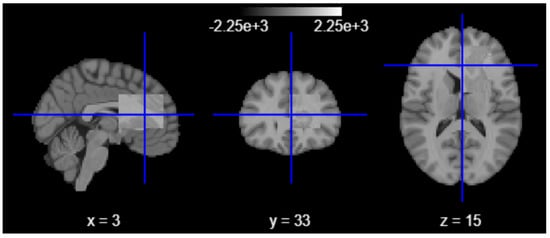

To further quantify and spatially contextualize hippocampal atrophy, we employed a second-level group-level statistical analysis using the nilearn neuroimaging library. T1-weighted scans were resampled, aligned, and modeled using a second-level GLM design matrix, contrasting low-volume subjects against those within normative ranges [35]. The resulting Z-statistical map revealed clusters of altered voxel intensities in hippocampal and adjacent limbic regions, offering group-level neuroanatomical evidence of structural deviation.

Figure 5.

Second-level group-level statistical analysis.